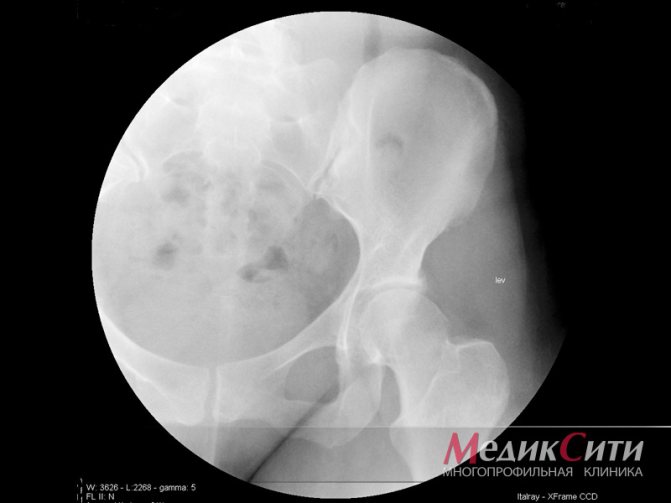

- Рентгенография позвоночника – позволяет обнаружить патологические изменения позвонков, характерные для спондилоартроза.

Рентгенологическое исследование. Часто является определяющим в постановке диагноза «спондилоартроз». На рентгенологическом снимке труднее распознать артроз суставов позвоночника, чем поражение более крупных суставов. Суставы позвоночника отличаются своим небольшим размером.

Однако рентгенологическая классификация стадий остеоартроза на них также распространяется:

- отсутствие рентгенологических признаков;

- сомнительные признаки;

- минимальные проявления в виде незначительного сужения суставных щелей и единичные остеофиты;

- умеренные проявления в виде прогрессирования сужения суставной щели и множественных остеофитов;

- выраженные проявления характеризуются практически полным отсутствием суставной щели и грубыми остеофитами.

Для того чтобы поставить правильный диагноз необходимо провести ряд исследований. Сначала врач назначает общий рентген позвоночника. Также для постановки диагноза помогут снимки отделов позвоночника, выполненные в разных плоскостях, так определяется спондилоартроз.

На них будут видны все изменения в формах суставов, а также образование наростов Заболевание может поражать и мягкие ткани около суставов.